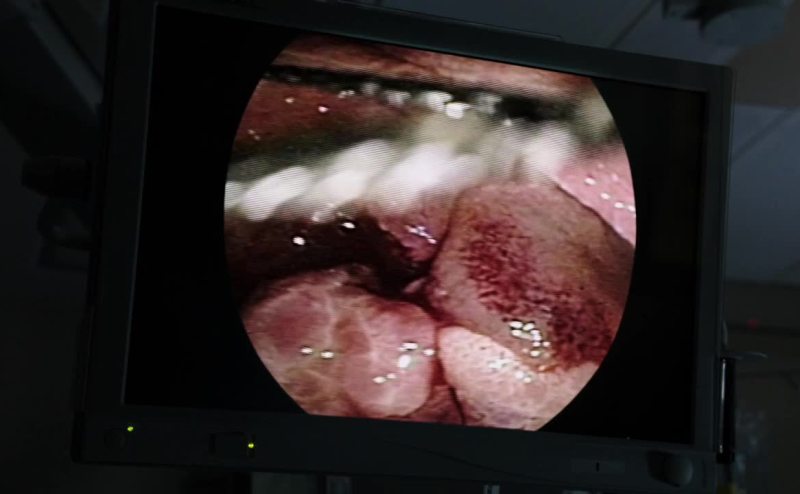

All right, that is the last of the fibroids.

And we're good.

Losing a lot of blood, Doc?

Not more than 100cc's.